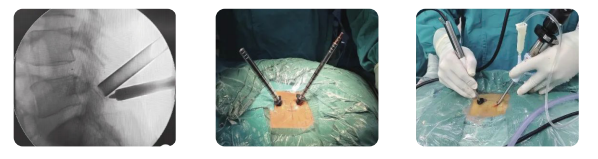

RF Surgical Spine Probe for Precise Disc Compression and Decompression

This RF surgical spine probe is specifically designed for precise disc compression and decompression procedures. It features low-temperature ablation and coagulation capabilities, allowing for controlled removal of disc tissues with minimal trauma. The probe is suitable for treating intervertebral disc disorders and can be used in minimally invasive surgeries to achieve effective decompression and quick postoperative relief

Features:

Low temperature resection and coagulation during Lumbar surgery.

One time use.

Abvious lumbar decompression after surgery.

Minimally Invasive, low temperature, stable operation

RF Surgical Spine Probe for Precise Disc Compression and Decompression Images |